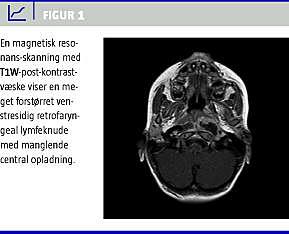

På mistanke om cervikal spondylodiscitis blev der bestilt knogleskintigrafi, og efter to gange bloddyrkning blev der påbegyndt behandling med penicillin og dicloxacillin givet intravenøst. Skintigrafien viste intet unormalt, hvorfor man supplerede med magnetisk resonans-skanning af cervikalcolumna. På skanningsbilledet sås en stor venstresidig RPA i en lymfeknude på 3,0 × 2,5 × 1,5 cm, der strakte sig fra basis cranii til C2 (Figur 1 ) med konveks indbuling i venstre side af oropharynx. Der blev ikke fundet ikke tegn til discitis. Begge bloddyrkninger var uden vækst.